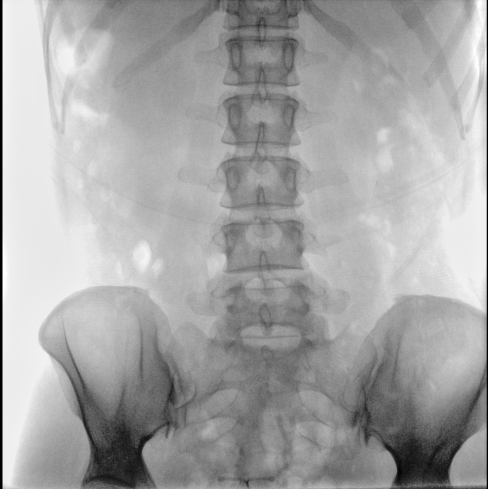

臨床應(yīng)用廣泛,適用于關(guān)節(jié)手術(shù)、創(chuàng)傷手術(shù)、脊柱手術(shù)、疼痛治療等。

●一屏雙顯,可同時觀察正側(cè)位圖像,便于對比觀察。